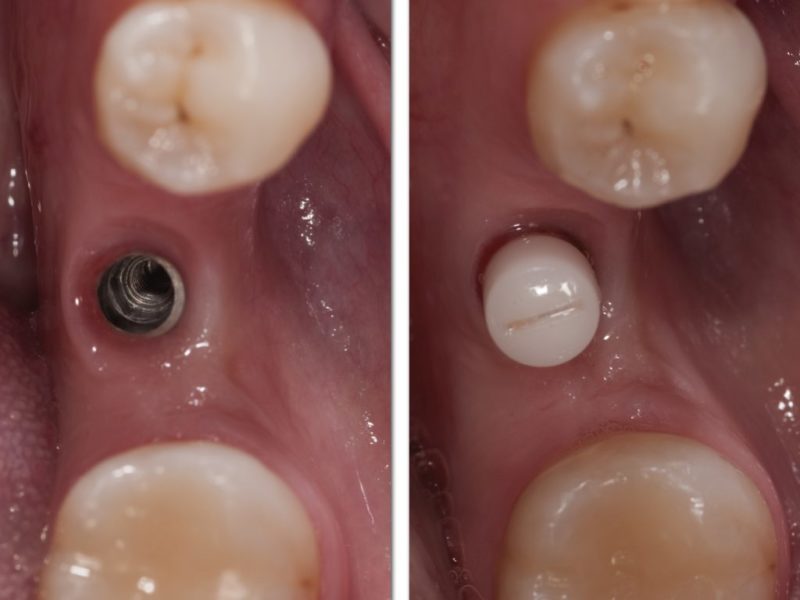

Single Implant With Angulated Peek Abutment

The loss of a single posterior tooth can cause the anatomical readaptation of tissues and it may lead to the loss of other teeth. This lady came to our office with one tooth missing, we advised the insertion of an implant with delayed load due to the non aesthetic positioning. After 6 months from the insertion of a 3P implant we took an impression with an open tray and a titanium transfer to ensure precision and developed a stone model on which we evaluated the diameter and the angulation of the abutment. We then inserted the proper 25° peek abutment and adapted to the spaces to fit the resin reconstruction. This first temporary rehabilitation is needed to shape the soft tissue. After a year a titanium abutment has been inserted on which we cemented a zirconia reconstruction.